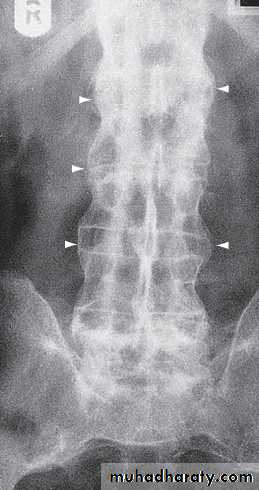

In chronic or recurrent disease, Xrays show periarticular osteoporosis, joint space narrowing and proliferative erosions.

Another characteristic feature is periostitis, especially of metatarsals, phalanges and pelvis, and large, ‘fluffy’ calcaneal spurs.

In contrast to AS, radiographic sacroiliitis is often asymmetrical and sometimes unilateral, and syndesmophytes are predominantly coarse and asymmetrical, often extending beyond the contours of the annulus (‘nonmarginal’)

Xray changes in the peripheral joints and spine are identical to those in psoriasis.

Xrays may be normal or show erosive change with joint space narrowing. Features that favour PsA over RA include the characteristic distribution of proliferative erosions with marked new bone formation, absence of periarticular osteoporosis and osteosclerosis.

Imaging of the axial skeleton often reveals features similar to those in chronic reactive arthritis, with coarse, asymmetrical, nonmarginal syndesmophytes and asymmetrical sacroiliitis.